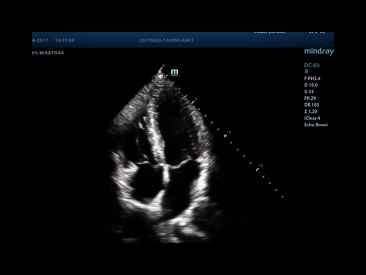

The best patient care is your ultimate goal. To achieve this requires confident diagnosis even with daily increases in patient throughput. Built on the foundation of MindrayвАЩs continuous customer insights into clinical needs and the inheritance from premium technology, the DC-80 with X-Insight is designed to help you manage your daily output with high efficiency, no matter what type patients and clinical challenges you will face.

eXceptional intelligence

Intelligence throughout entire workflow